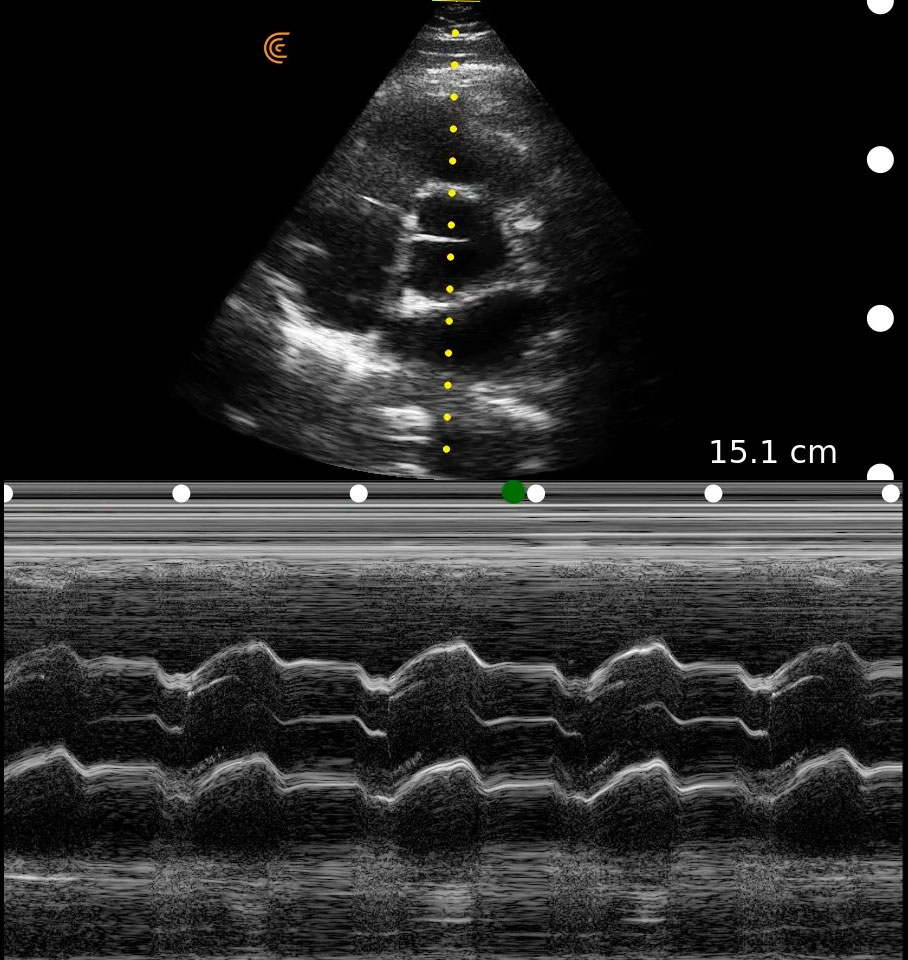

Medical professionals love the high portability, easy of use, and high-definition imaging of the Clarius C3 HD3 multipurpose scanner for full body imaging up to 40 cm. It’s the leading choice for medical professionals looking for premium imaging in an affordable scanner. Artificial intelligence, specialized presets and customizable workflows automatically optimize imaging for a seamless experience.

Applications: Abdominal, Cardiac, Lung, OB/GYN, Superficial

Clinical Images